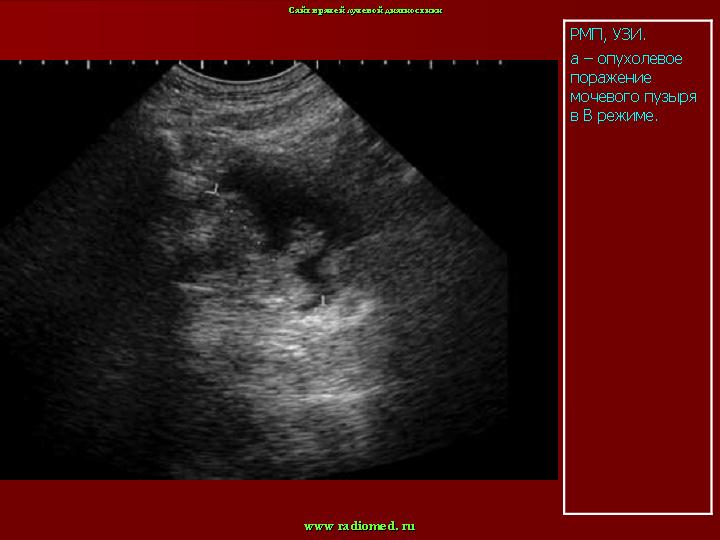

При подозрении на опухоль мочевого пузыря обследование больного следует начинать с ультразвукового исследования. При этом используют трансабдоминальное, трансректальное и внутрипузырное исследование. Оно всегда должно проводиться при заполненном мочевом пузыре. При этом можно определить и документировать объем мочевого пузыря, наличие и количество остаточной мочи после мочеиспускания, наличие опухолевых разрастаний в пузыре, их локализацию, размеры, количество, взаимоотношения с шейкой пузыря, реже - степень прорастания стенки, т.е. стадию заболевания.

При выполнении трансабдоминальной ультрасонографии большие трудности возникают при выявлении опухолей, расположенных на передней стенке мочевого пузыря. Лишь в тех случаях, когда величина опухоли превышает 3 см, ее можно обнаружить при ультразвуковом наружном сканировании. Однако оценить степень местного распространения опухоли этой локализации с помощью трансабдоминальной ультрасонографии не представляется возможным. Большинство исследователей, изучавших информативность трансабдоминальной ультрасонографии в определении степени выраженности местного распространения злокачественного процесса у больных раком мочевого пузыря, отмечают существенные ограничения этого метода [4, 14, 19]. Показано, что трансабдоминальная ультрасо-нография является недостаточно информативным методом распознавания начальных стадий рака мочевого пузыря, особенно в тех случаях, когда опухоль локализуется на передней стенке органа [6, 17, 23, 25]. Это обусловлено препятствиями по ходу ультразвукового луча при выполнении трансабдоминальной ультрасонографии (большой массив тканей, лонное сочленение). Они затрудняют визуализацию всех отделов мочевого пузыря. В этих случаях применение эндовезикального ультразвукового сканирования оказывает существенную помощь в диагностике.